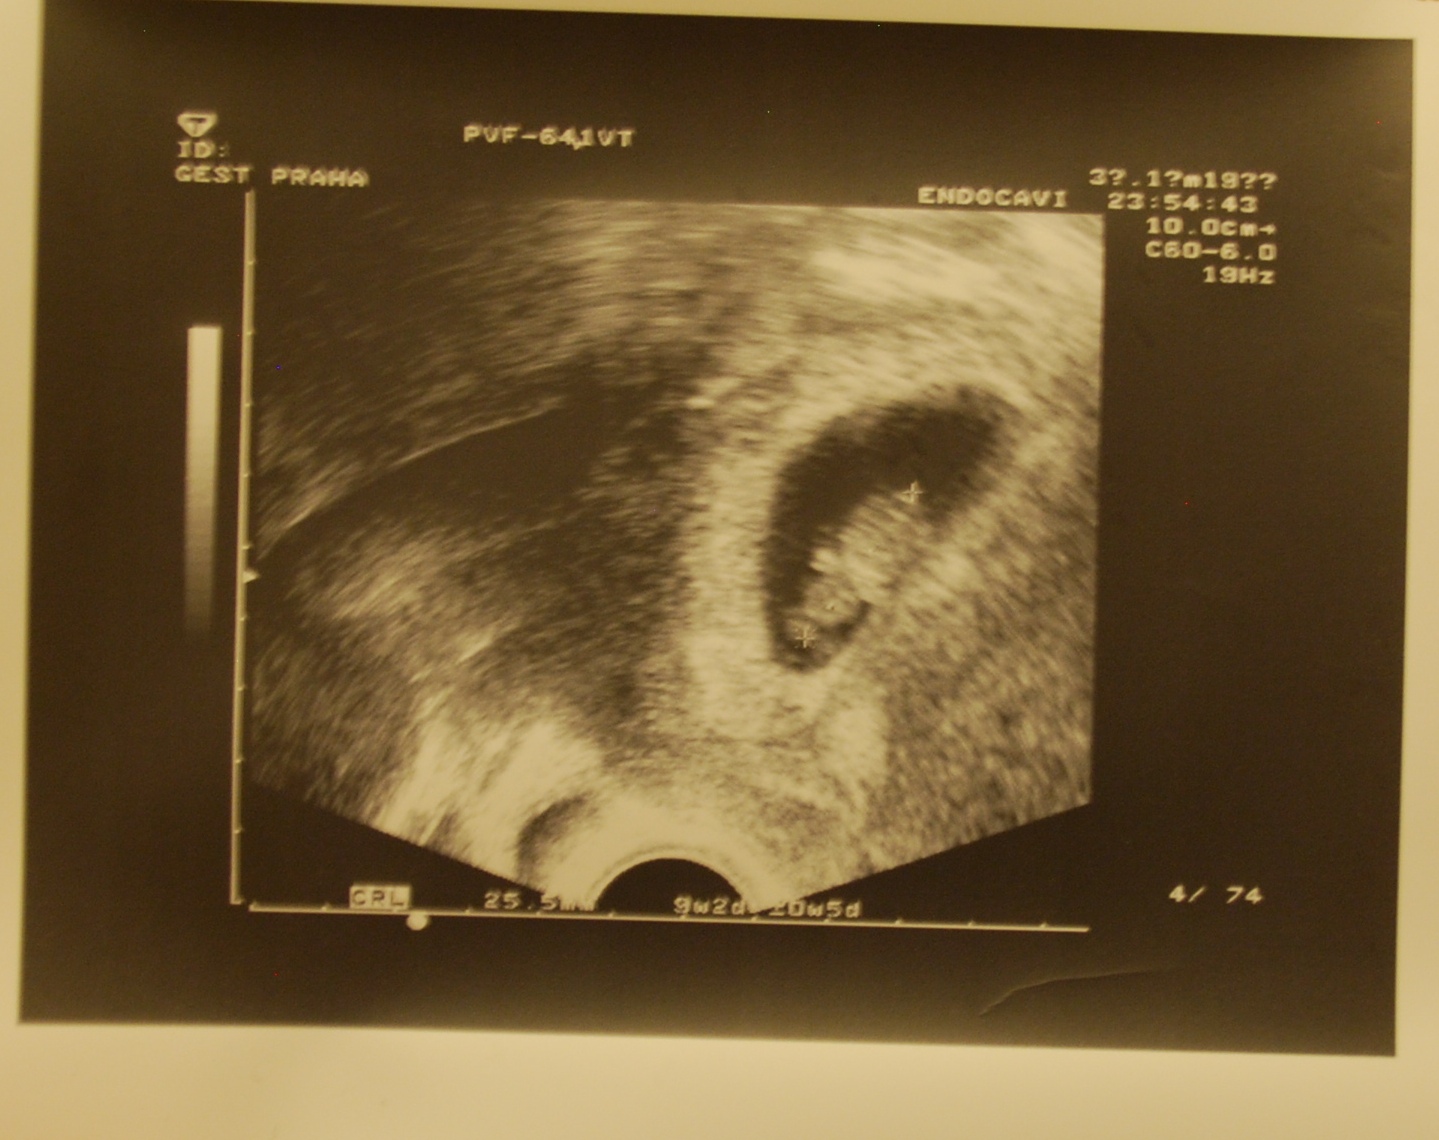

| Ve věku přibližně 9+2 :o) |